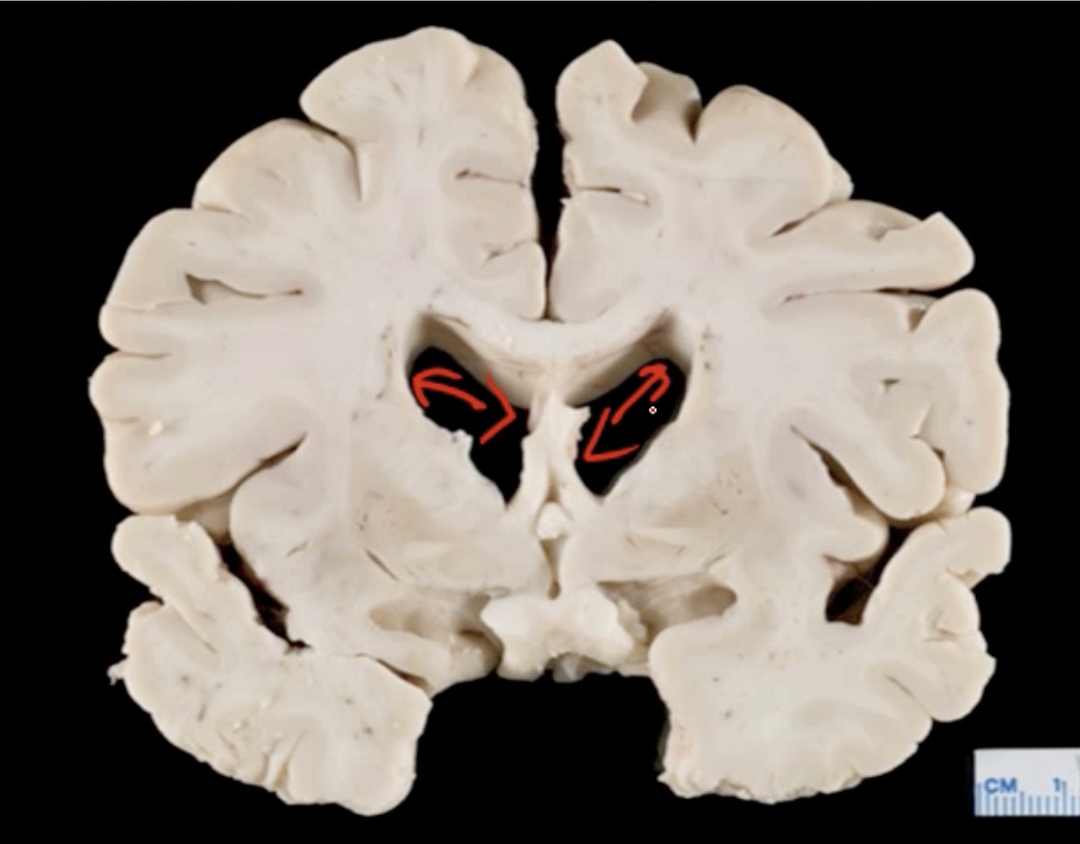

What is this?

-pt has AIDs

Which organism caused this?

Toxoplasma gondii